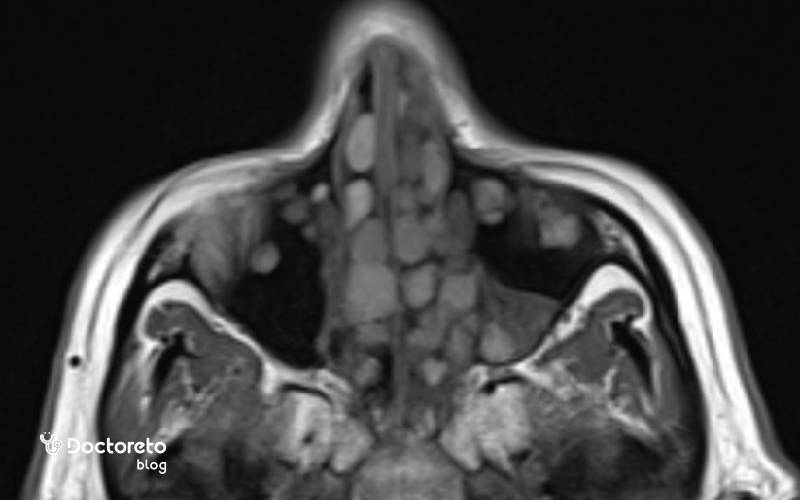

عکس پولیپ بینی در سی تی اسکن

سیتیاسکن سینوسها یکی از روشهای اصلی تصویربرداری برای بررسی پولیپ بینی است. در سی تی اسکن پولیپ بینی، پولیپها معمولا به صورت نواحی با تراکم نرم در داخل سینوسها یا حفره بینی دیده میشوند که به جای فضای پر از هوا، بافت یا مایع را نشان میدهند. سیتیاسکن به پزشک کمک میکند بسنجد چه میزان از سینوسها درگیر است، آیا مسیر تخلیه سینوسها مسدود شده، و آیا تغییرات استخوانی یا انحراف بینی وجود دارد یا نه. این اطلاعات بهویژه قبل از جراحی پولیپ بینی برای برنامهریزی دقیق عمل ضروری است.